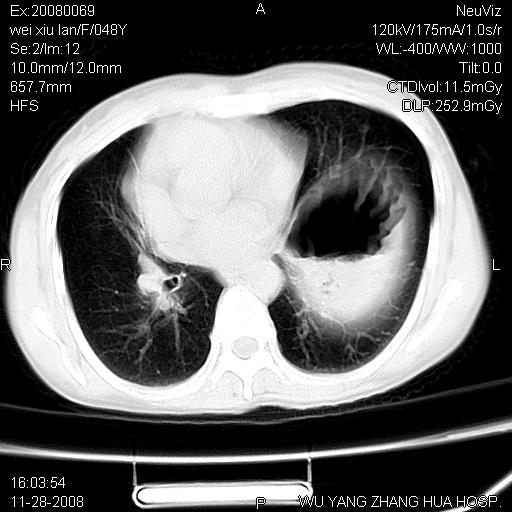

标题: CT16847:女,48岁,咳嗽,发热两日,平常偶有上腹部不适。 [打印本页]

标题: CT16847:女,48岁,咳嗽,发热两日,平常偶有上腹部不适。

能否考虑食管裂孔疝?请老师们多多指教。

这个是左侧膈膨升伴不完全性胃翻转,手术将松弛的左横膈膜折叠缝合即解决问题。

支持左侧膈疝,心脏受压右移.

左下肺不张、膈膨升,胸腔胃

胃、脾脏及部分肠管明显升高,并压迫心脏移位,

首先考虑:左侧膈疝。

左侧胸腔内见胃肠及脾脏影

支持膈疝

左膈顶及肋膈角均上移,膈面光滑,考虑左膈肌麻痹